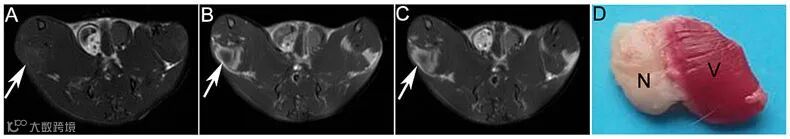

其中GdL1在体外显示了优异的磁共振性质,其弛豫率分别为7.28,显著高于临床上常用造影剂Gd-DOTA(4.28);并且具有很好的体外稳定性及水溶性。同时,从大鼠缺血再灌注肝坏死模型以及肌肉坏死模型的磁共振成像上可以看到,GdL1实现了对坏死肝脏和坏死肌肉的清晰在体成像,明显区分坏死组织与正常组织,显示出良好的坏死靶向性。

Figure 3. MR images and corresponding TTC staining images of rats with muscular necrosis. A-D were images of rats with muscular necrosis at pre-injection and 0 h, 3 h post-injection of GdL1 (0.1 mmol/kg) and corresponding TTC staining images of necrotic muscle. White arrow shows the necrotic muscle, Necrosis (N), Viable (V).